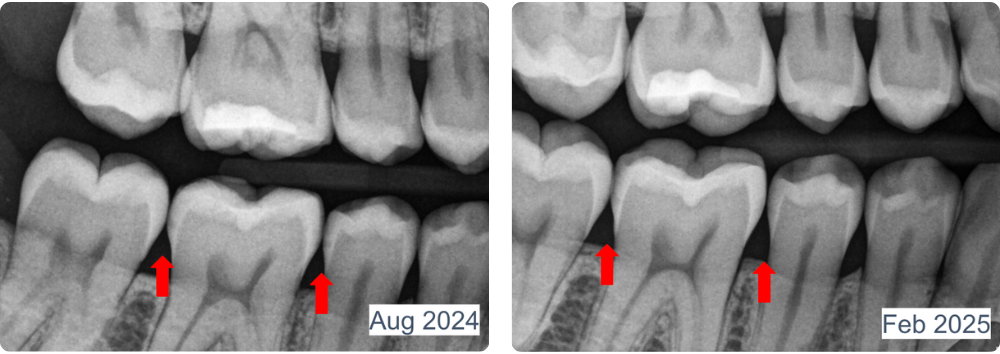

“In february of this year we took bitewings on this patient and diagnosed a need for fillings on #15-MO and 10-MO. Due to life circumstances, the patient did not return for her restorative appointment. She did start using Dr. Jen’s superpaste at that time due to high caries risk. She returned in August for her next hygiene appointment and we decided to take bitewings again to see how far the decay had progressed. I was blown away at the new images!! I wish I had a video of the doctor doing the exam, looking at #18 on the radiograph, checking the patients mouth, going back to the radiograph again, leaning back and pondering everything he knows about remineralization.”

April C. , RDH